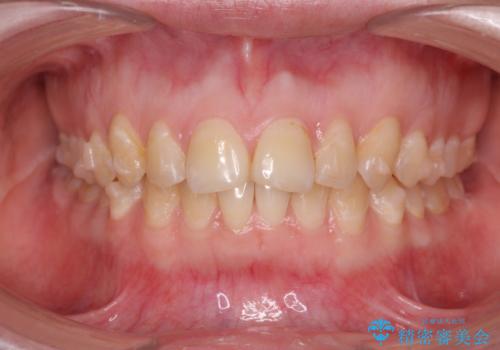

マウスピース矯正で行う出っ歯の治療

- 飛び出したように見える前歯の改善を求めて来院されました。

元々、セラミッククラウンですぐに歯並びを改善したいと希望されていましたが、目立たないマウスピース矯正治療のご提案を行なったところ矯正治療による歯並びの改善を選択されました。

矯正治療を行ったことで出っ歯の改善とともに安定した噛み合わせも手に入れることができました。